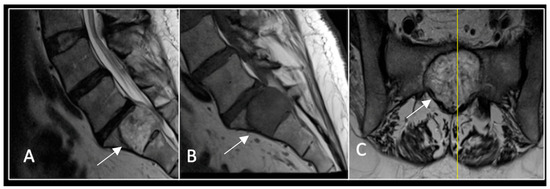

Figure 5.

MRI imaging following separation surgery. (A) T2W sagittal; (B) T1W sagittal; (C) T2W axial. Imaging shows removal of posterior lumbosacral elements with residual disease (arrow) within the S1 vertebral body but significant reduction in tumour dimensions. The yellow line on the sagittal images indicates the level at which the axial image was obtained.